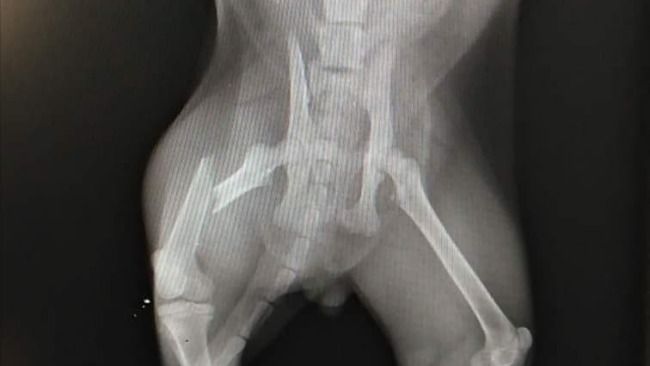

Kotek Femurek trafił do współpracującej z portalami Koty.pl i Psy.pl lekarz weterynarii Doroty Cibor. Po przeprowadzonych badaniach okazało się, że zwierzę ma złamaną łapkę. W celu jej poskładania niezbędne będzie umieszczenie drutu wewnątrz kości. To kosztowna operacja. Mężczyzna, który przygarnął pod swój dach mruczka, a po wypadku przywiózł go do lecznicy, niestety nie jest w stanie opłacić kosztów leczenia. W tej sytuacji rozważał nawet uśpienie zwierzęcia. Ostatecznie opiekę nad kotem przekazał pani Dorocie, która natychmiast zaczęła działać.